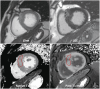

This document is the third part of the guidelines for the protocol, the interpretation and post-processing of cardiac magnetic resonance (CMR) studies. These consensus recommendations have been developed by the Consensus Committee of the Korean Society of Cardiovascular Imaging to standardize the requirements for image interpretation and post-processing of CMR. This third part of the recommendations describes tissue characterization modules, including perfusion, late gadolinium enhancement, and T1- and T2 mapping. Additionally, this document provides guidance for visual and quantitative assessment consisting of "What-to-See," "How-To," and common pitfalls for the analysis of each module. The Consensus Committee hopes that this document will contribute to the standardization of image interpretation and post-processing of CMR studies.